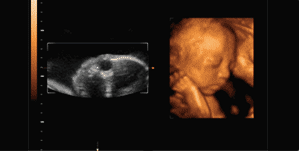

什么是四维彩超?

也就是4D超声波技术,是目前世界上最先进的彩色超声技术。四维成像技术(4D),能直观、立体显示人体器官的三维结构及动态、实时地观察立体结构,而以往的二维成像技术只能显示人体器官的某一切面。

四维容积超声解决方案

Voluson 30年前发明了三维成像,一直持续创新,不断扩展四维超声的应用范围及适应症,一直在引领三维/四维容积发展方向。

胎儿四维成像

四维彩超能够对胎儿进行超声检查,立体显示胎儿的手脚、脸、各器官的发育情况,还可以观察到胎儿在母体里的动态,对胎儿畸形,如唇裂、腭裂、骨骼发育异常、心血管畸形等能进行早期诊断。